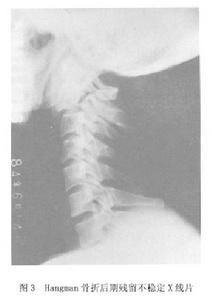

視造成局部不穩的原因、類型部位及具體情況鵻不同其臨床與X線表現差異較大鵻因器質性病變所引起鵻的健康搜尋不穩(顱底凹陷症 齒突骨折脫位後等)症狀多較重;而僅僅由於動力性因素引起的暫時性不穩 症狀則較輕 多表現為椎-基底動脈供血不全症狀健康搜尋。病程長 發病緩慢者其症狀較輕,而急性發生者的症狀重使椎管矢狀徑變寬的損傷(如Hangman骨折、寰椎分離性骨折等)後期殘留健康搜尋的不穩,從X線片上看十分明顯但臨床症狀卻輕(圖3);而使椎管變狹窄的損傷鵻 其表現當然較重。由於上述各種原因,本病的臨床症狀及影像學所見特點可相差甚大,在觀察判定與診斷上需全面考慮但仍應以臨床為主。